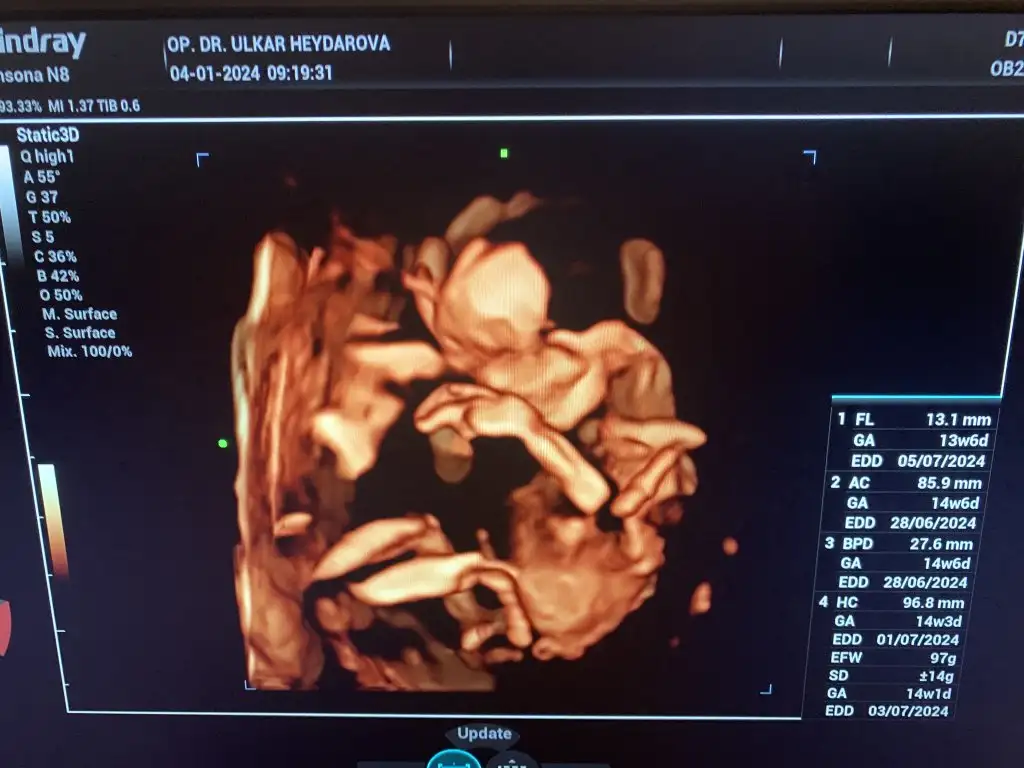

banada bakar mısınız kızlar bebişim sizce kız mı erkek mi?Merhaba ilk doktorum %70 kız dedi değişebilir dedi şuan 14. Haftayım görüntü de bişey söylemedi değişti mi yoksa kız mı? Anlamıyorum![]()

![]()